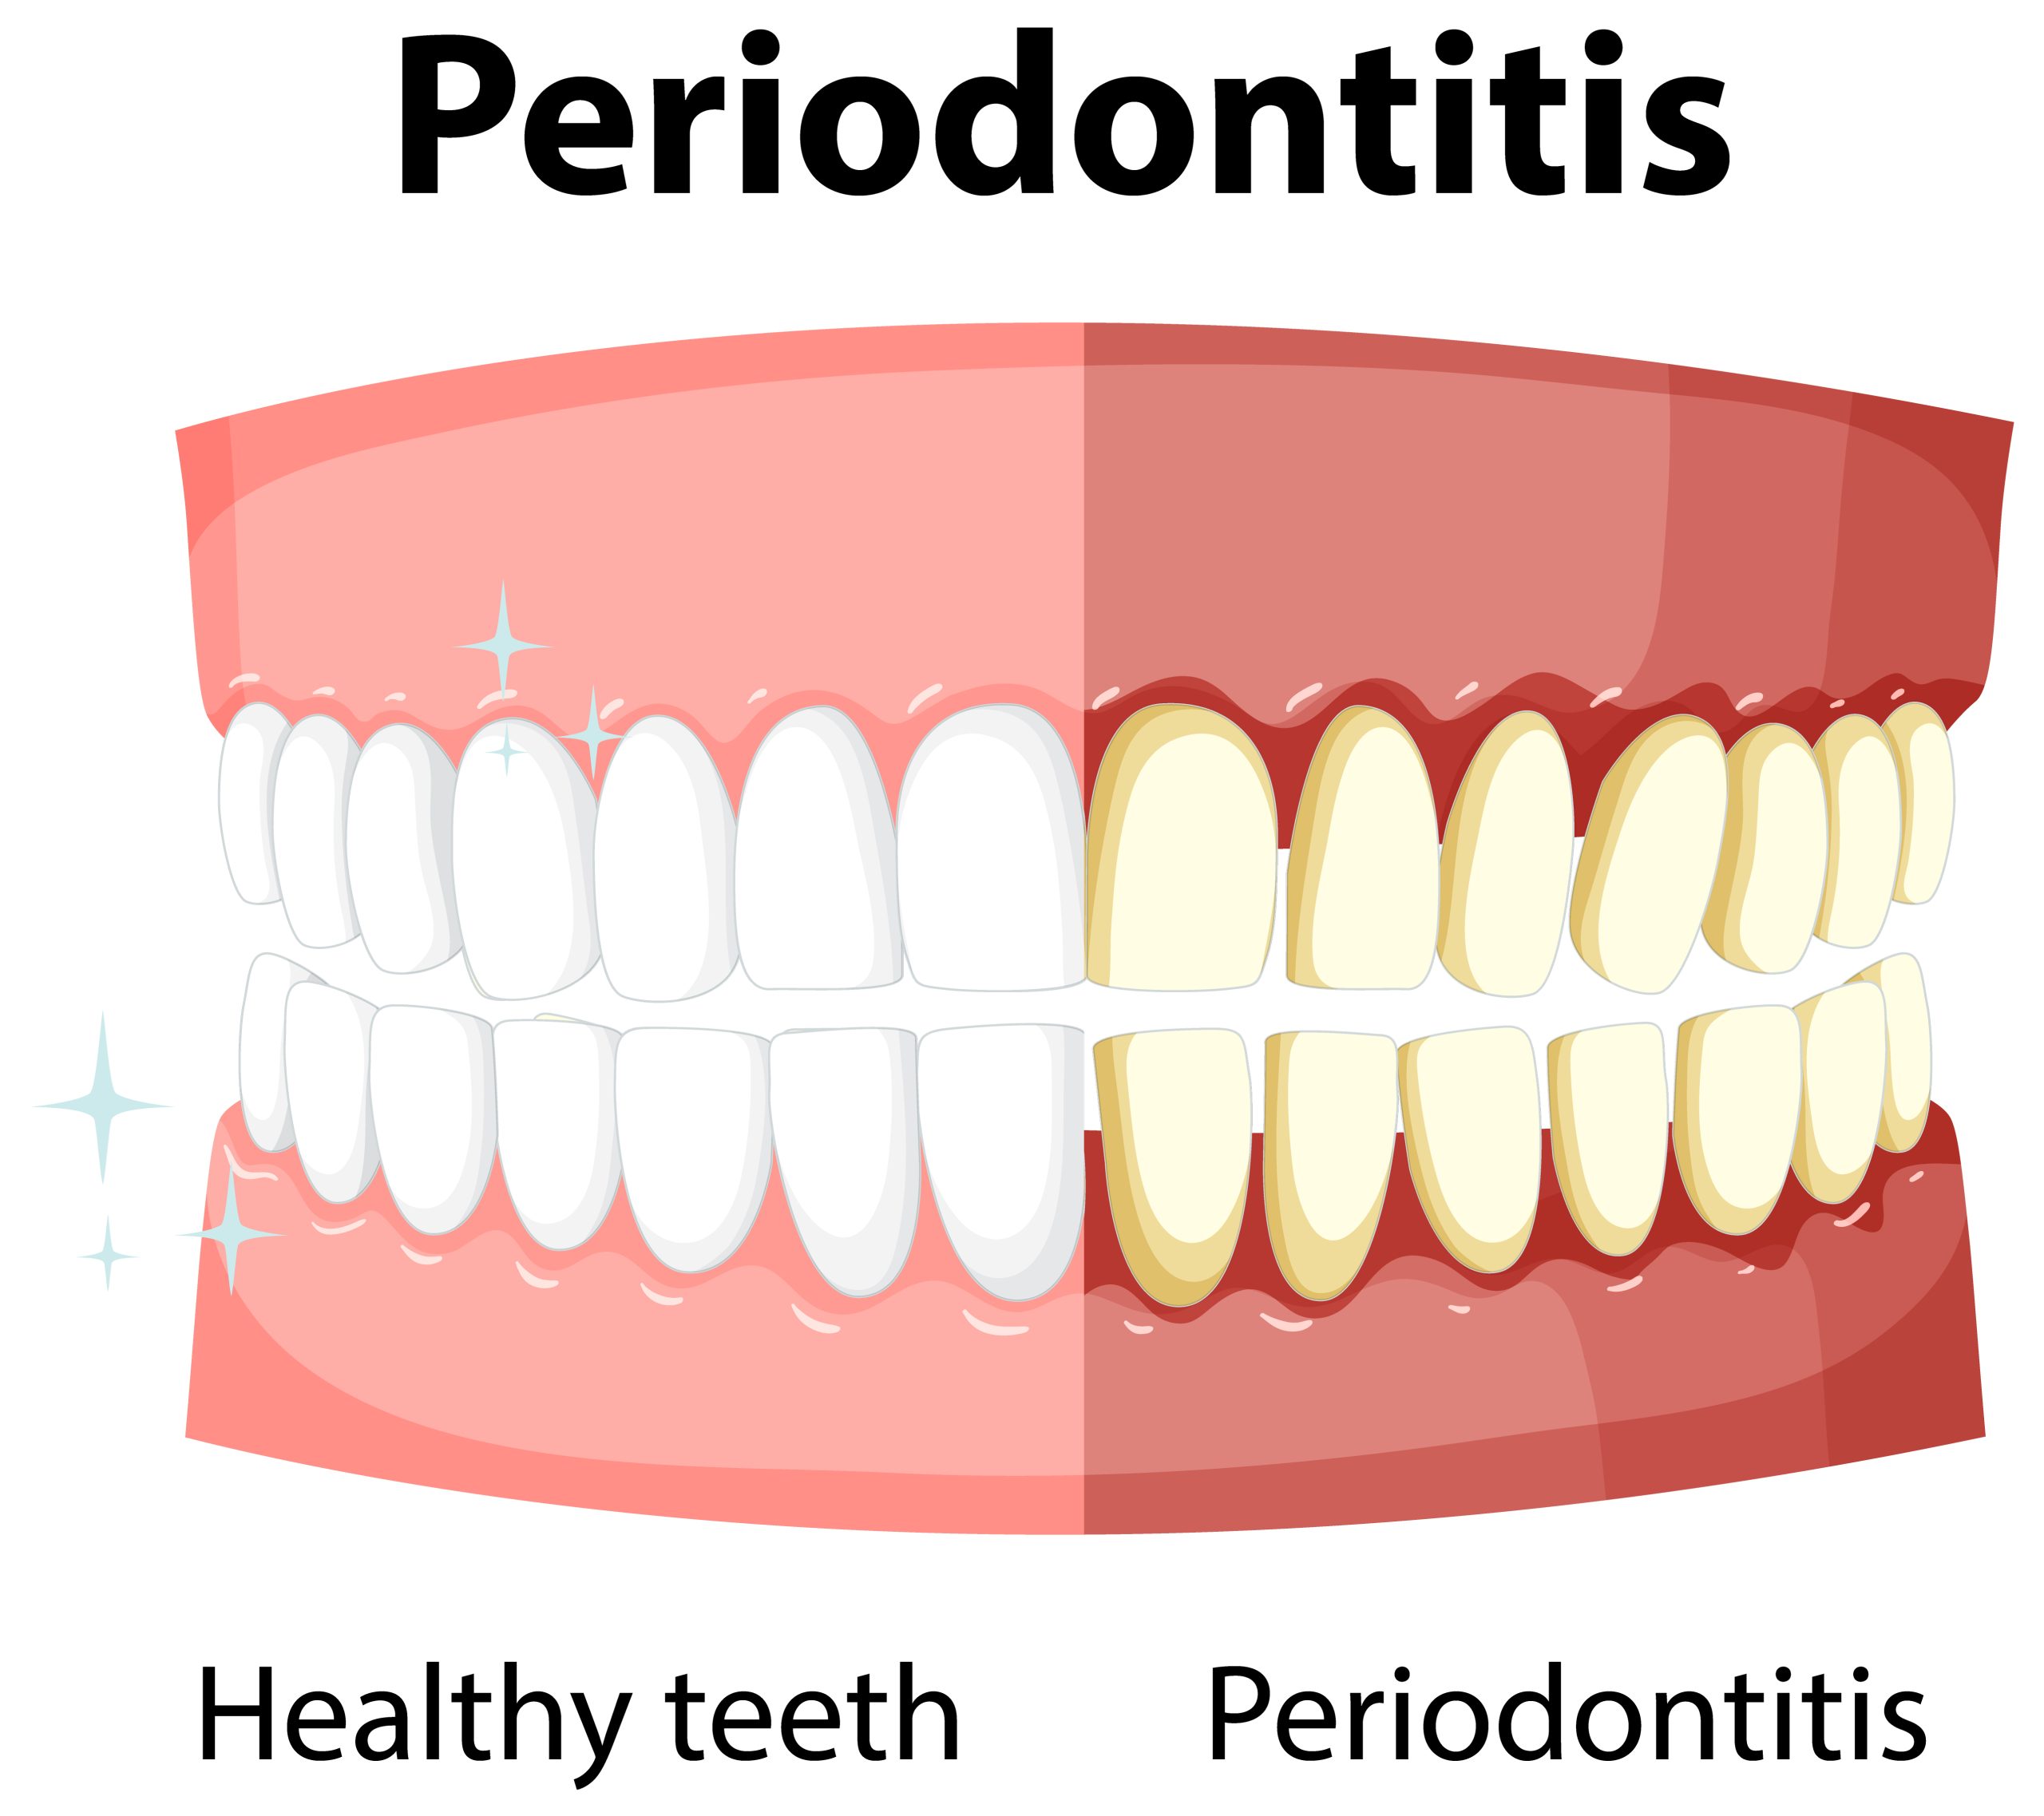

Gum disease, also known as periodontal disease, is an infection and inflammation of the tissues that support your teeth.

There are two main stages: